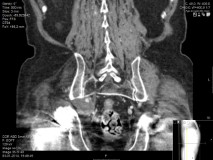

CT angiography (Figure 3) of the lower limb confirmed the aneurysmal origin of the sciatic nerve compression lesion with origin on the right internal iliac artery. It was completely occluded with a thrombosed aneurysm with approximately 4x5cm.

Figure 3 CT- angiography showing right internal iliac artery aneurysm.